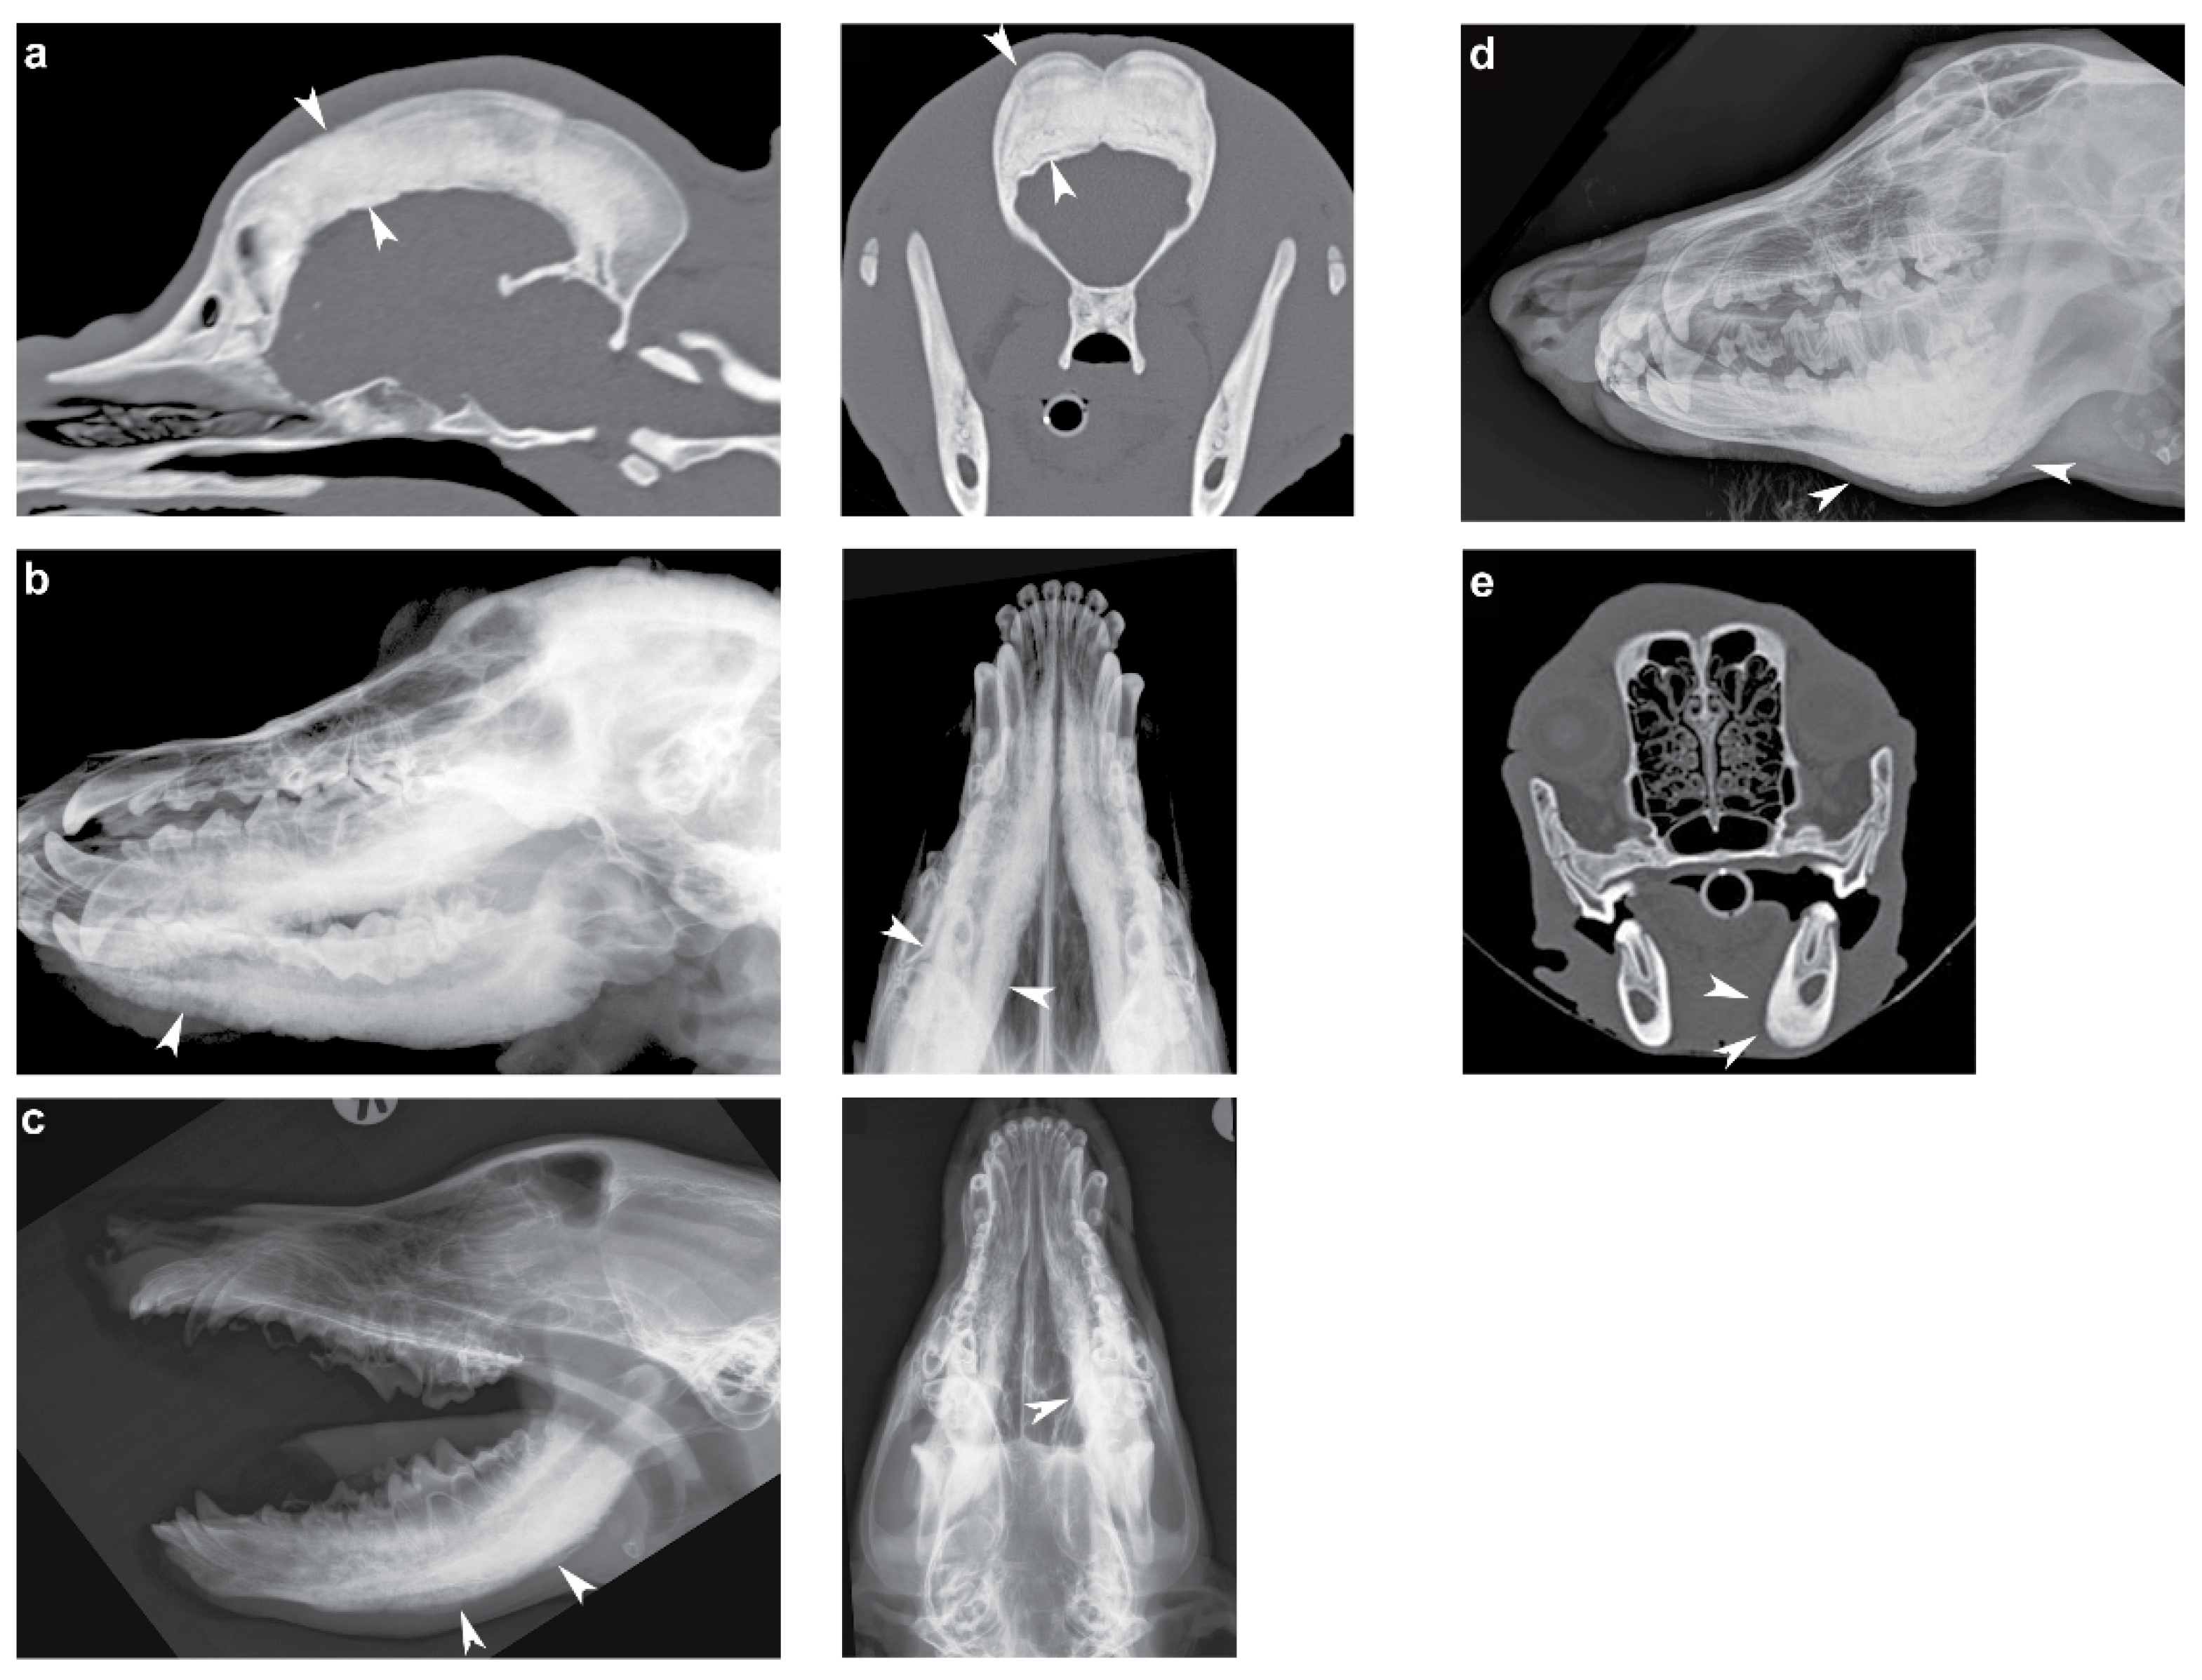

We investigated a CHS-affected American Staffordshire Terrier and seven CMO-affected dogs of different breeds (Australian Terrier, Basset Hound, Cairn Terrier, Curly Coated Retriever, German Wirehaired Pointer, Old English Sheepdog, and Weimaraner). The diagnosis was made by veterinarians observing the typical clinical signs including persistent and sharp pain when opening mouth, painful swelling of the jaw, fever, and in some cases also severe pain of ulna and radius bones. Age of onset of the clinical signs ranged from 3 to 7 months of age, and skull radiographs/computed tomographic (CT) images were available for six of the affected dogs (Supplementary Table S1). The imaging findings of one dog was consistent with CHS and in four dogs with CMO (Figure 1), in the remaining dog, no changes were identified on radiographs, but clinical signs were consistent with the diagnosis of CMO. Due to the self-regressive course of the disorder, the remission of clinical signs appeared in all cases soon after the diagnosis and symptomatic treatment. On the basis of the previously published gene test, all eight collected dogs were genotyped negative for the reported CMO-causing variant in SLC37A2 (XM_005619600.3:c.1332C>T) [11]. In addition, for all eight dogs, the region of the SLC37A2 gene was also manually inspected in IGV to confirm no candidate variants were missed in the functional annotation and to rule out obvious, large structural variants including copy number variation affecting this gene.

Figure 1.

Radiographs/computed tomographic (CT) images of the craniomandibular osteopathy (CMO)/calvarial hyperostotic syndrome (CHS)-affected dogs. (a) Sagittal and transverse CT images of an American Staffordshire Terrier showing severe thickening of the calvarial diploic bone (arrowheads). (b) Ventrolateral-dorsolateral oblique and ventrodorsal skull radiographs illustrating a palisading periosteal new bone formation along the mandible of a Basset Hound (arrowheads). (c) Open mouth laterolateral and ventrodorsal view of the skull of a German Wirehaired Pointer showing periosteal new bone formation along the mandible (arrowheads). (d) Slightly oblique laterolateral view of the mandible of an Old English Sheepdog showing similar periosteal new bone formation along the mandible (arrowheads). (e) Transverse CT image of a Weimeraner with the arrowheads pointing towards the periosteal new bone formation at the ventral and medial aspect of the left mandibular corpus.